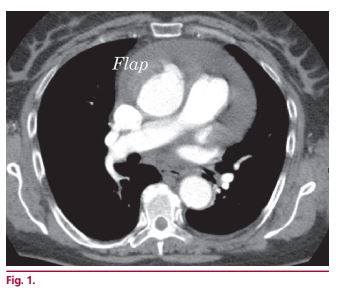

Doble úlcera penetrante de aorta ascendente

IMÁGENES EN CARDIOLOGÍA